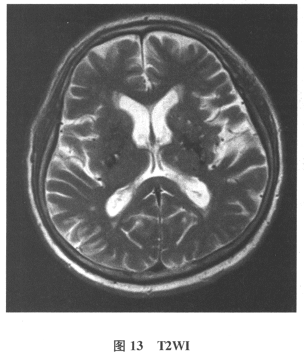

[多选题]患者男,61岁。因“发作性头晕2年,加重伴记忆力下降、走路不稳3月余”就诊。查体:BP140/70mmHg;意识清楚,构音障碍,近期记忆力及远期记忆力

[单选题]患者男,61岁。因“发作性头晕2年,加重伴记忆力下降、走路不稳3月余”就诊。查体:BP140/70mmHg;意识清楚,构音障碍,近期记忆力及远期记忆力